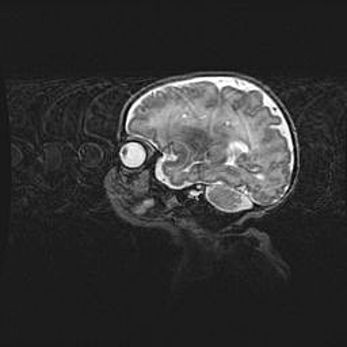

Подострая гематома правой гемисферы мозжечка.

Наружная гидроцефалия.

Возраст: 15 дней

Вес: 3100 г

Пол: женский

Окружность головы: 37 см

Срок гестации: 35-36 недель

При открытой наружной форме гидроцефалии у новорожденных расширяются и переполняются субарахноидные пространства.

Кровоизлияния в мозжечок имеют две клинико-анатомические формы: полушарные гематомы и кровоизлияния в червь.

К появлению этой патологии может привести: повреждения головного мозга, возникающие в результате асфиксии и гипоксии плода при беременности, или травмы во время родов. Редко гематома мозжечка может быть результатом первичной коагулопатии и сосудистой мальформации, диссеминированном внутрисосудистом свертывании, изоиммунной тромбоцитопении.